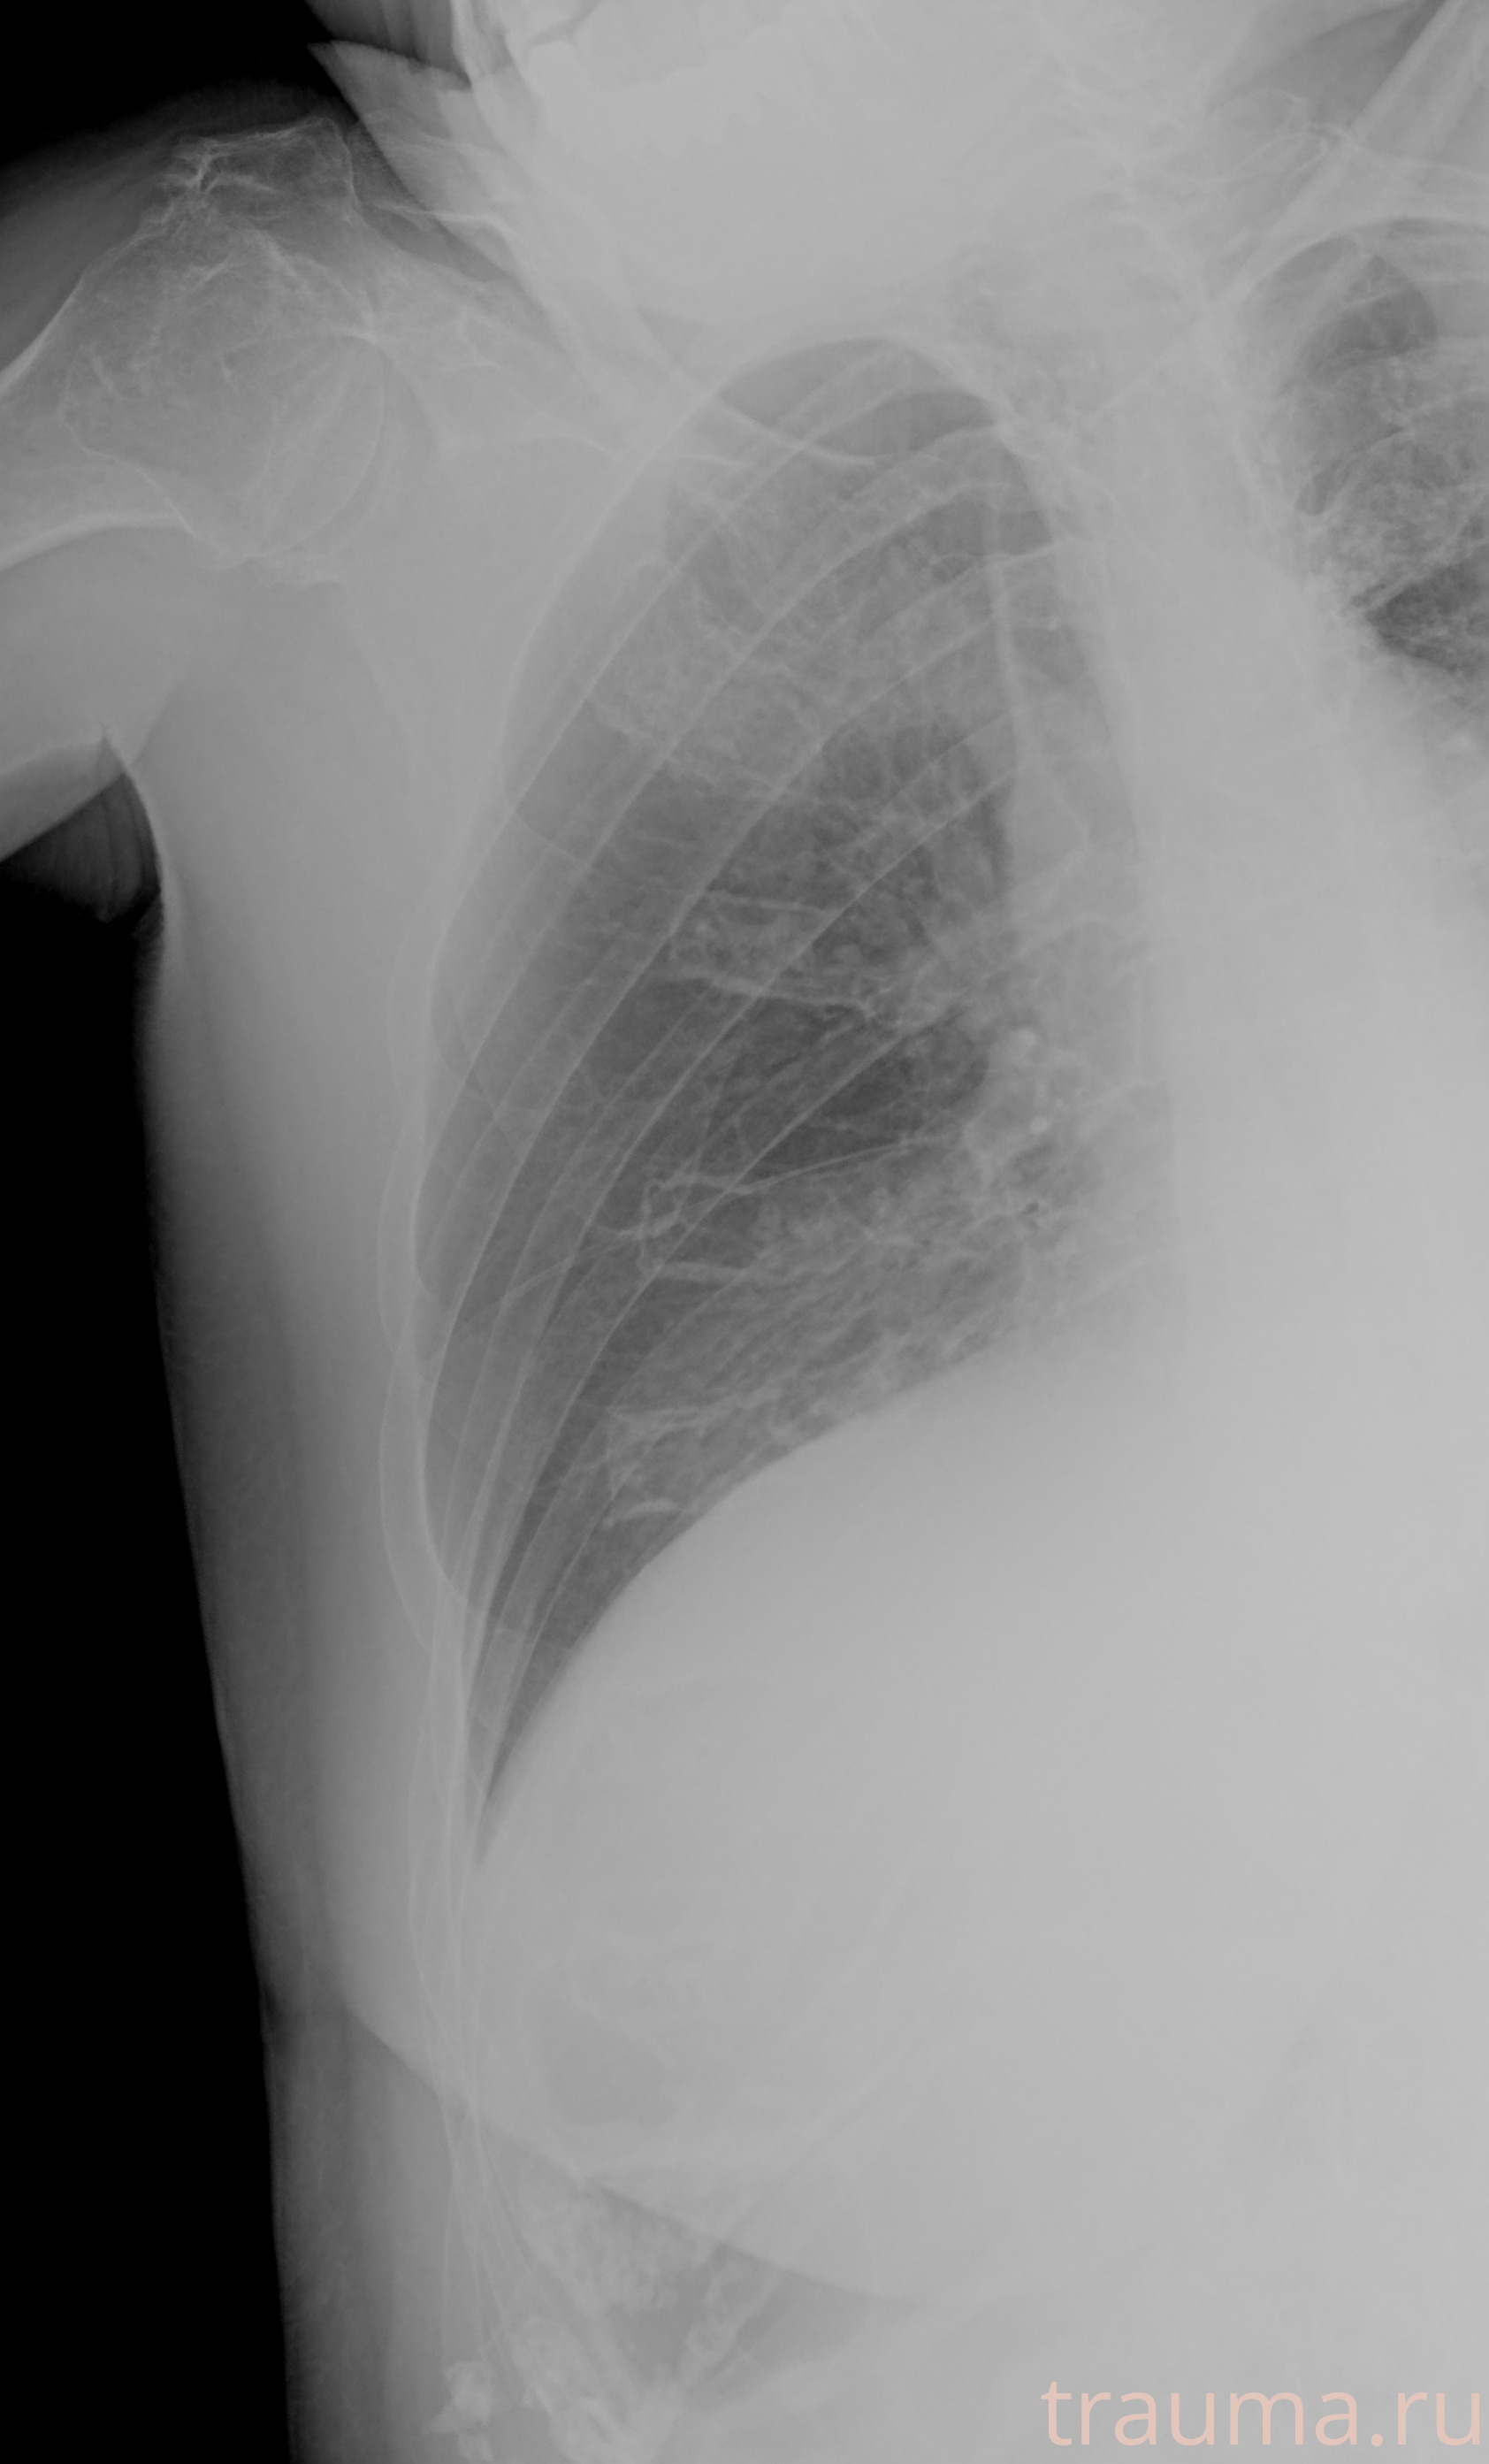

Рентгенограммы

Рентген на дому: по вашему адресу приезжает врач-рентгенолог, травматолог-ортопед с мобильным рентгеновским аппаратом, проводит диагностику травмы или заболевания, делает необходимые рентгенограммы, дает рекомендации по дальнейшему лечению. Получить качественные снимки в домашних условиях возможно благодаря уникальной методике, разработанной МосРентген Центром для института  Склифосовского